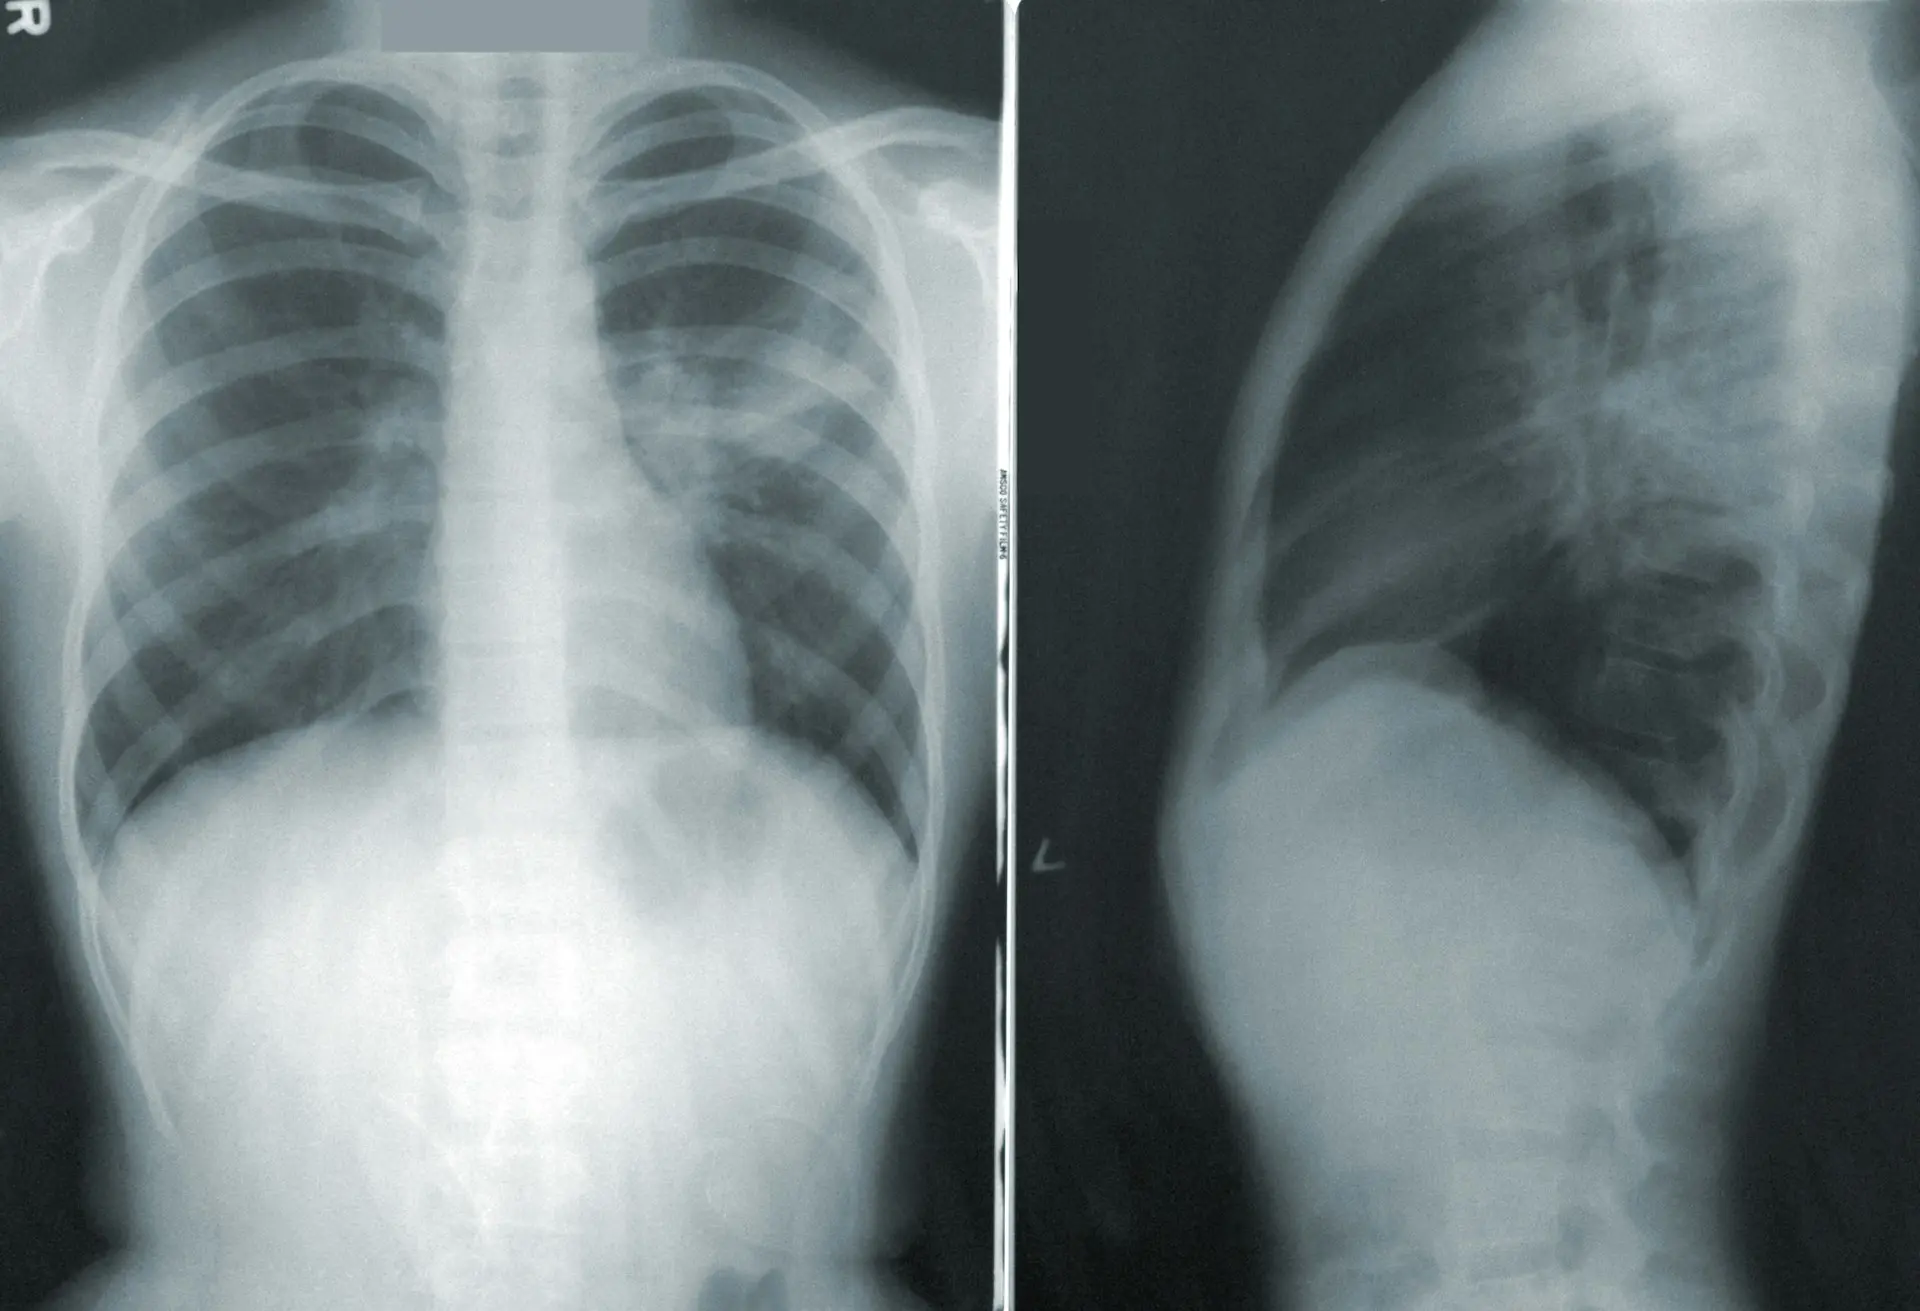

Ważnym elementem diagnostyki jest obrazowe badanie płucLink otwiera się w nowej karcie. Zwykle wykonuje się RTG klatki piersiowej. Na zdjęciu rentgenowskim można zaobserwować obecność powietrza w jamie opłucnej oraz zapadnięcie płuca. W niektórych przypadkach może być konieczne wykonanie tomografii komputerowej klatki piersiowej w celu dokładniejszej oceny stanu.